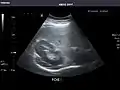

Abdominal Ultrasound (Full Exam)

STRUCTURED REPORT

(Technique: Transabdominal ultrasonography; Device: Toshiba Aplio XG)

Liver: Diffusely homogeneous and normal in echogenicity. No focal mass or contour nodularity. No intrahepatic biliary ductal dilatation.

Portal Vein: Patent main portal vein.

Gallbladder: No stones, wall thickening, or pericholecystic fluid.

Common Bile Duct: Nondilated measuring 1.3 mm at the level of the porta hepatis.

Pancreas: Visualized portions unremarkable.

Spleen: Normal in size.

Kidneys: Right and left kidneys measure 11.5 cm and 12 cm in length respectively. No hydronephrosis. Small left lower pole kidney cyst.

Ascites: None.

Aorta: Visualized portions normal in caliber, 16 x 15 mm.

IVC: Normal.

IMPRESSION:

Normal abdominal ultrasound.